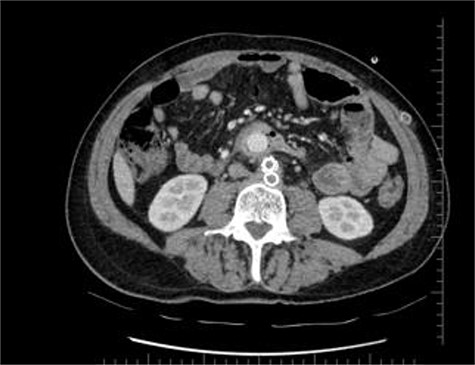

Axial section shows the two limbs of the EVAR, at the bottom. And on top of it, the Dacron straight graft part in the middle of the jejenum.

During the first days of December 2018, the patient visited another medical center because of fatigue, difficulty in breathing, lower back pain and inability to walk. His blood biochemistry revealed a very high CRP level (350 mg/dl), and complete blood count revealed a very high level of white blood cells (21 000/ul). An abdominal CT scan illustrated part of the graft was totally eroded into the small intestine (Figs 1–3). The patient was referred to my office and an infectious disease specialist. He had high body temperature (39.5°C) and was lying on the bed with lower extremities adducted to the chest. Antibiotic and supportive treatment was started. Emergency surgery was performed. We found an 8–10 cm of the straight part of the graft had become totally incorporated into the proximal part of the jejenum. The graft was freed, and 10–15 cm of the jejenum was resected and anastomosed. The area was irrigated with saline and hypochlorous acid. We then put a 20 x 10 composite mesh between the vascular graft and the intestine using a non-adhensive surface facing the intestine to prevent future graft and intestine interactions and erosion. After hemostasis, two drains were placed retroperitonally, and the abdomen was closed. On the fourth post-operative day, a high body temperature and high CRP levels were recorded. An abdominal CT revealed retroperitoneal abcess formation. During relaparotomy, the anastomosis was found to be intact, and the retroperitoneal abscess was drained and irrigated with saline. The drains were reinserted. After a month, he once again started to have high fever and high CRP levels. Again, an abdominal CT revealed abscess formation. This time, the abscess was approached transcutaneously. By making an incision in the proximal left lomber region, the abscess was drained. Another incision was made distally, and two drains were placed in the retroperitoneal area.